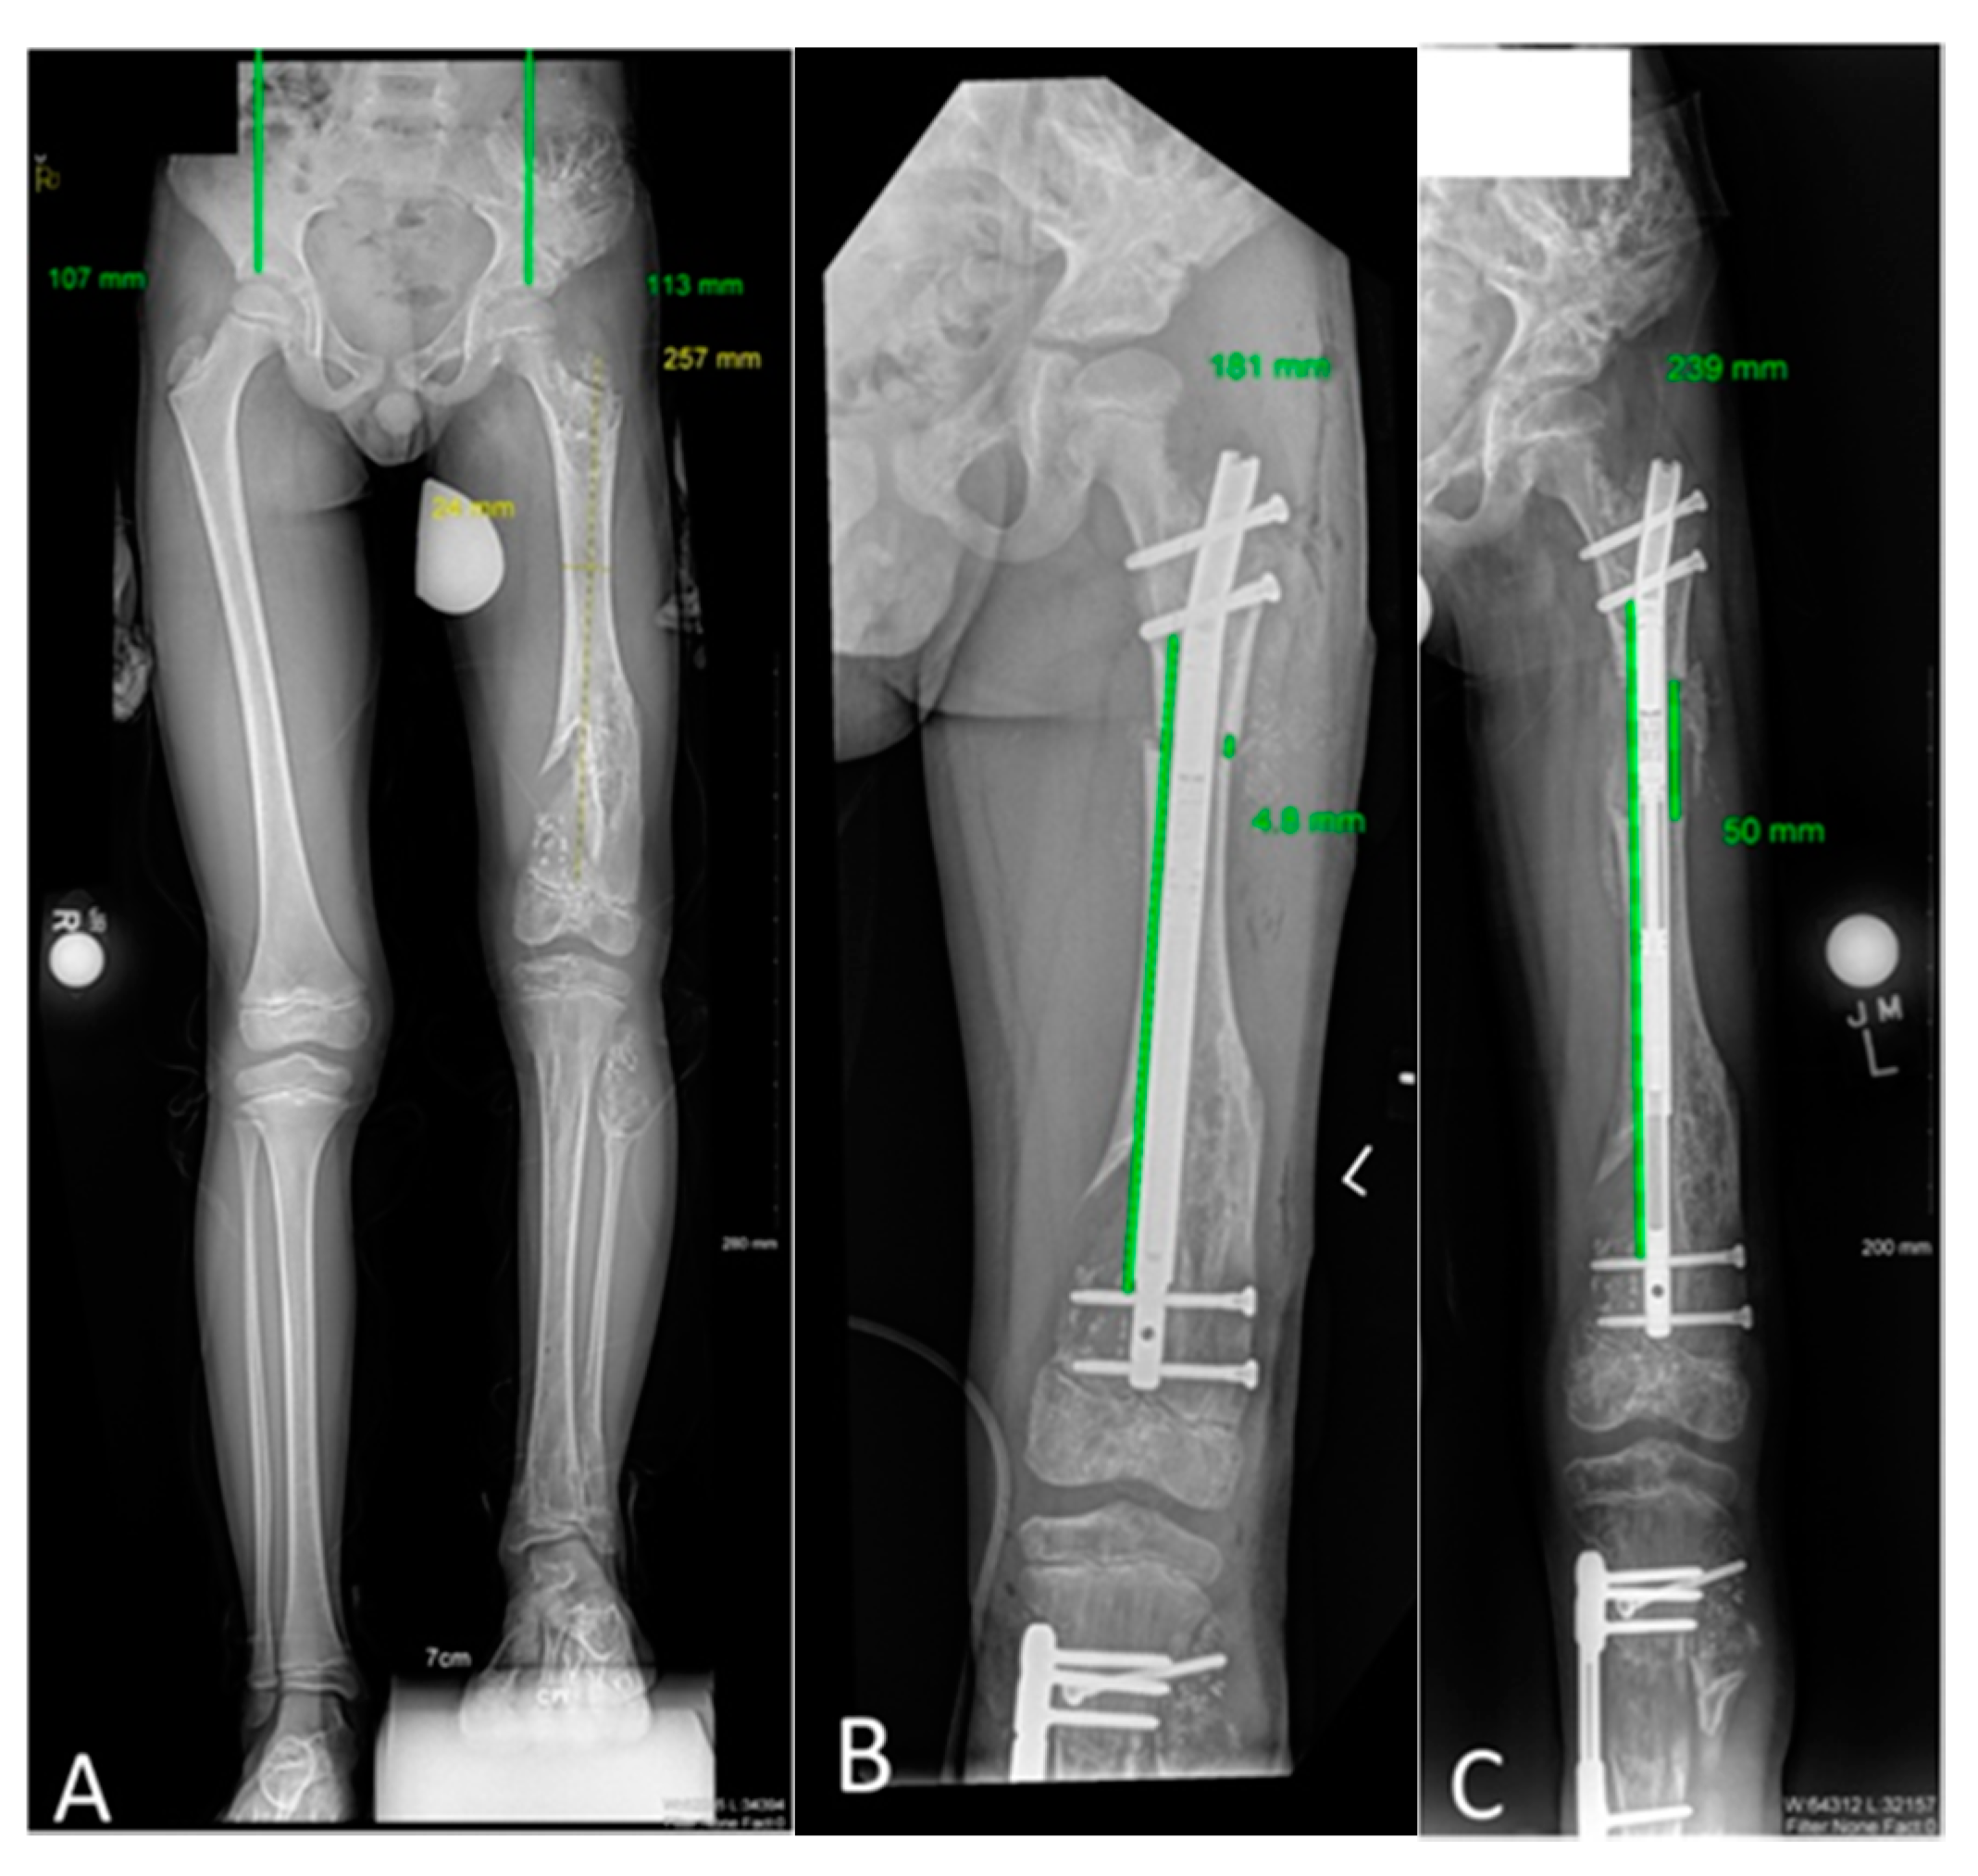

Figure 3. Acute coronal plane deformity correction with simultaneous intramedullary motorized nail lengthening. This figure portrays Patient 7’s first lengthening experience. (A) An 8-year old male with enchondromatosis predominantly affecting the left femur, radiographically consistent with Ollier’s disease. Left leg shorter than right by 122 mm, predicted to be 184 mm at maturity. Coronal full leg length radiography identifies additional substantial left genu valgus deformity mainly occurring in the distal femur. (B) Lateral radiograph identifies no sagittal plane deformity requiring correction. (C,D) Anterior–posterior and lateral immediate postoperative radiographs demonstrating acute coronal correction via an osteotomy and plate internal fixation strategy, with simultaneous lengthening nail inserted with a proximal osteotomy where lengthening will occur. (E) Full length standing radiograph taken upon completion of 50 mm uncomplicated lengthening. The coronal deformity is improved. (F) The patient is suboptimally positioned for the lateral radiograph which was not repeated at the time, but is shown to demonstrate no sagittal plane deformity occurred through the femur during the lengthening process. (G) The patient’s current full length radiograph after his third lengthening identifies 41 mm residual LLD, with slight genu valgum progression compared to the initially provided correction. A final lengthening surgery with repeat acute coronal plane correction is planned following skeletal maturity.